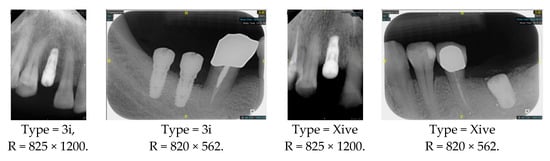

| Image Size | 825 × 1200 or 820 × 562 | Image format | DCI |

| The dataset includes two implant brands: 3i and Xive | |||

| 3i | 164 | Xive | 77 |